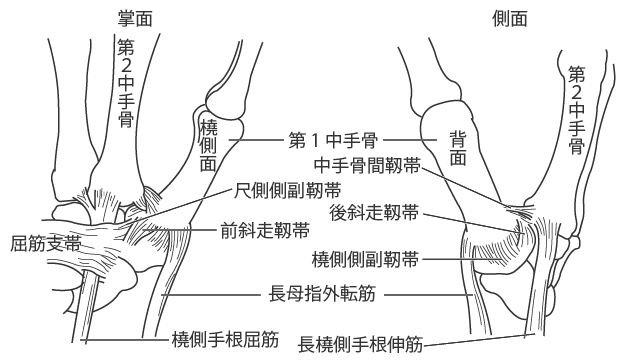

- 靱帯再建:損傷した靱帯の一部を、別の結合組織片から作成した移植片で置き換えます。